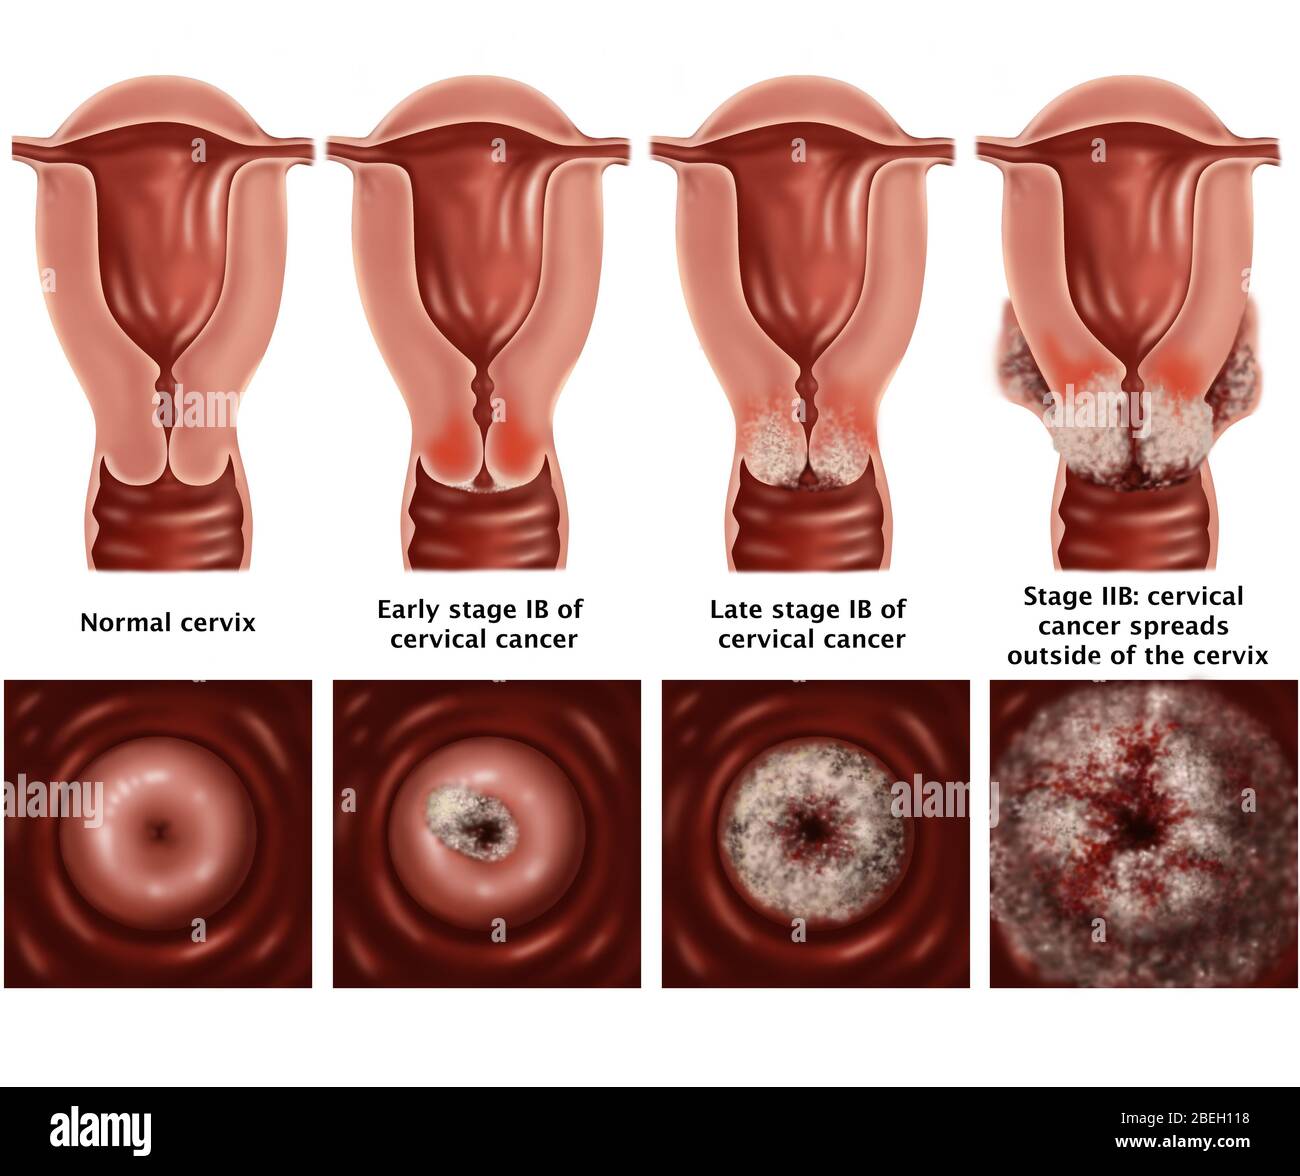

Кондиломы - это одно из самых распространенных заболеваний, передающихся половым путем. Они вызваны вирусом папилломы человека (ВПЧ) и могут появляться на внешних половых органах, анусе, ротовой полости и других областях тела.

Симптомы кондилом могут варьироваться, и визуальное представление этого заболевания может быть различным. Некоторые кондиломы выглядят как небольшие бугорки или бородавки, в то время как другие могут иметь форму плоских пятен или цветных наростов.